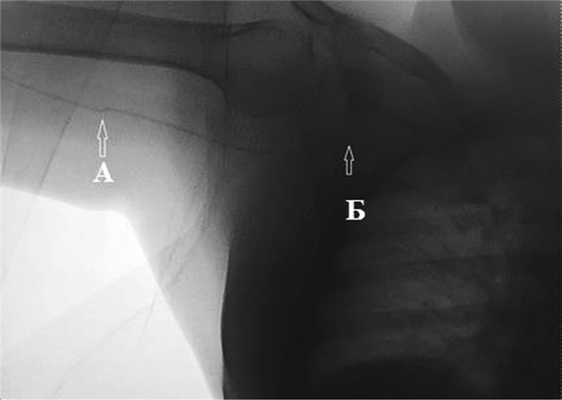

В стационаре при осмотре в месте выхода катетера не было признаков локального воспаления, отсутствовали признаки инфекции кровотока. При проверке работоспособности катетера выявлена его дисфункция: инфузия через катетер происходила, однако аспирация крови была невозможна, что позволило заподозрить формирование клапана на дистальном отверстии катетера. Выполнена рентгенография, при которой выявлена дислокация дистального конца катетера, который обнаружен в подключичной вене (рис. 1). Рис. 1. Изгиб катетера на уровне верхней трети плеча (А), дистальный конец ПИЦВК в подключичной вене (Б).

При попытке удаления катетера путем тракции возникло ощущение сопротивления. Больная направлена в рентгенооперационную, где выявлено, что при попытках удаления катетера препятствие возникало на уровне верхней трети плеча, где имелся перегиб катетера (см. рис. 1). С техническими сложностями по катетеру через этот изгиб проведен гидрофобный гибкий металлический проводник в правую брахиоцефальную вену. Несмотря на это, удалить катетер при тракции по-прежнему не представлялось возможным.